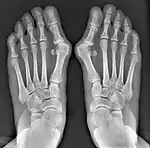

![]() Fig. 8a. Painful hallux valgus and metatarsus primus varus deformity recurrence of left foot after osteotomy surgery | |

- For recurrence correction after osteotomy procedure (Fig. 8)

Late deformity recurrence can happen after osteotomy (bone-breaking) procedures because osteotomy surgeries do not specifically stabilize first metatarsal bone.